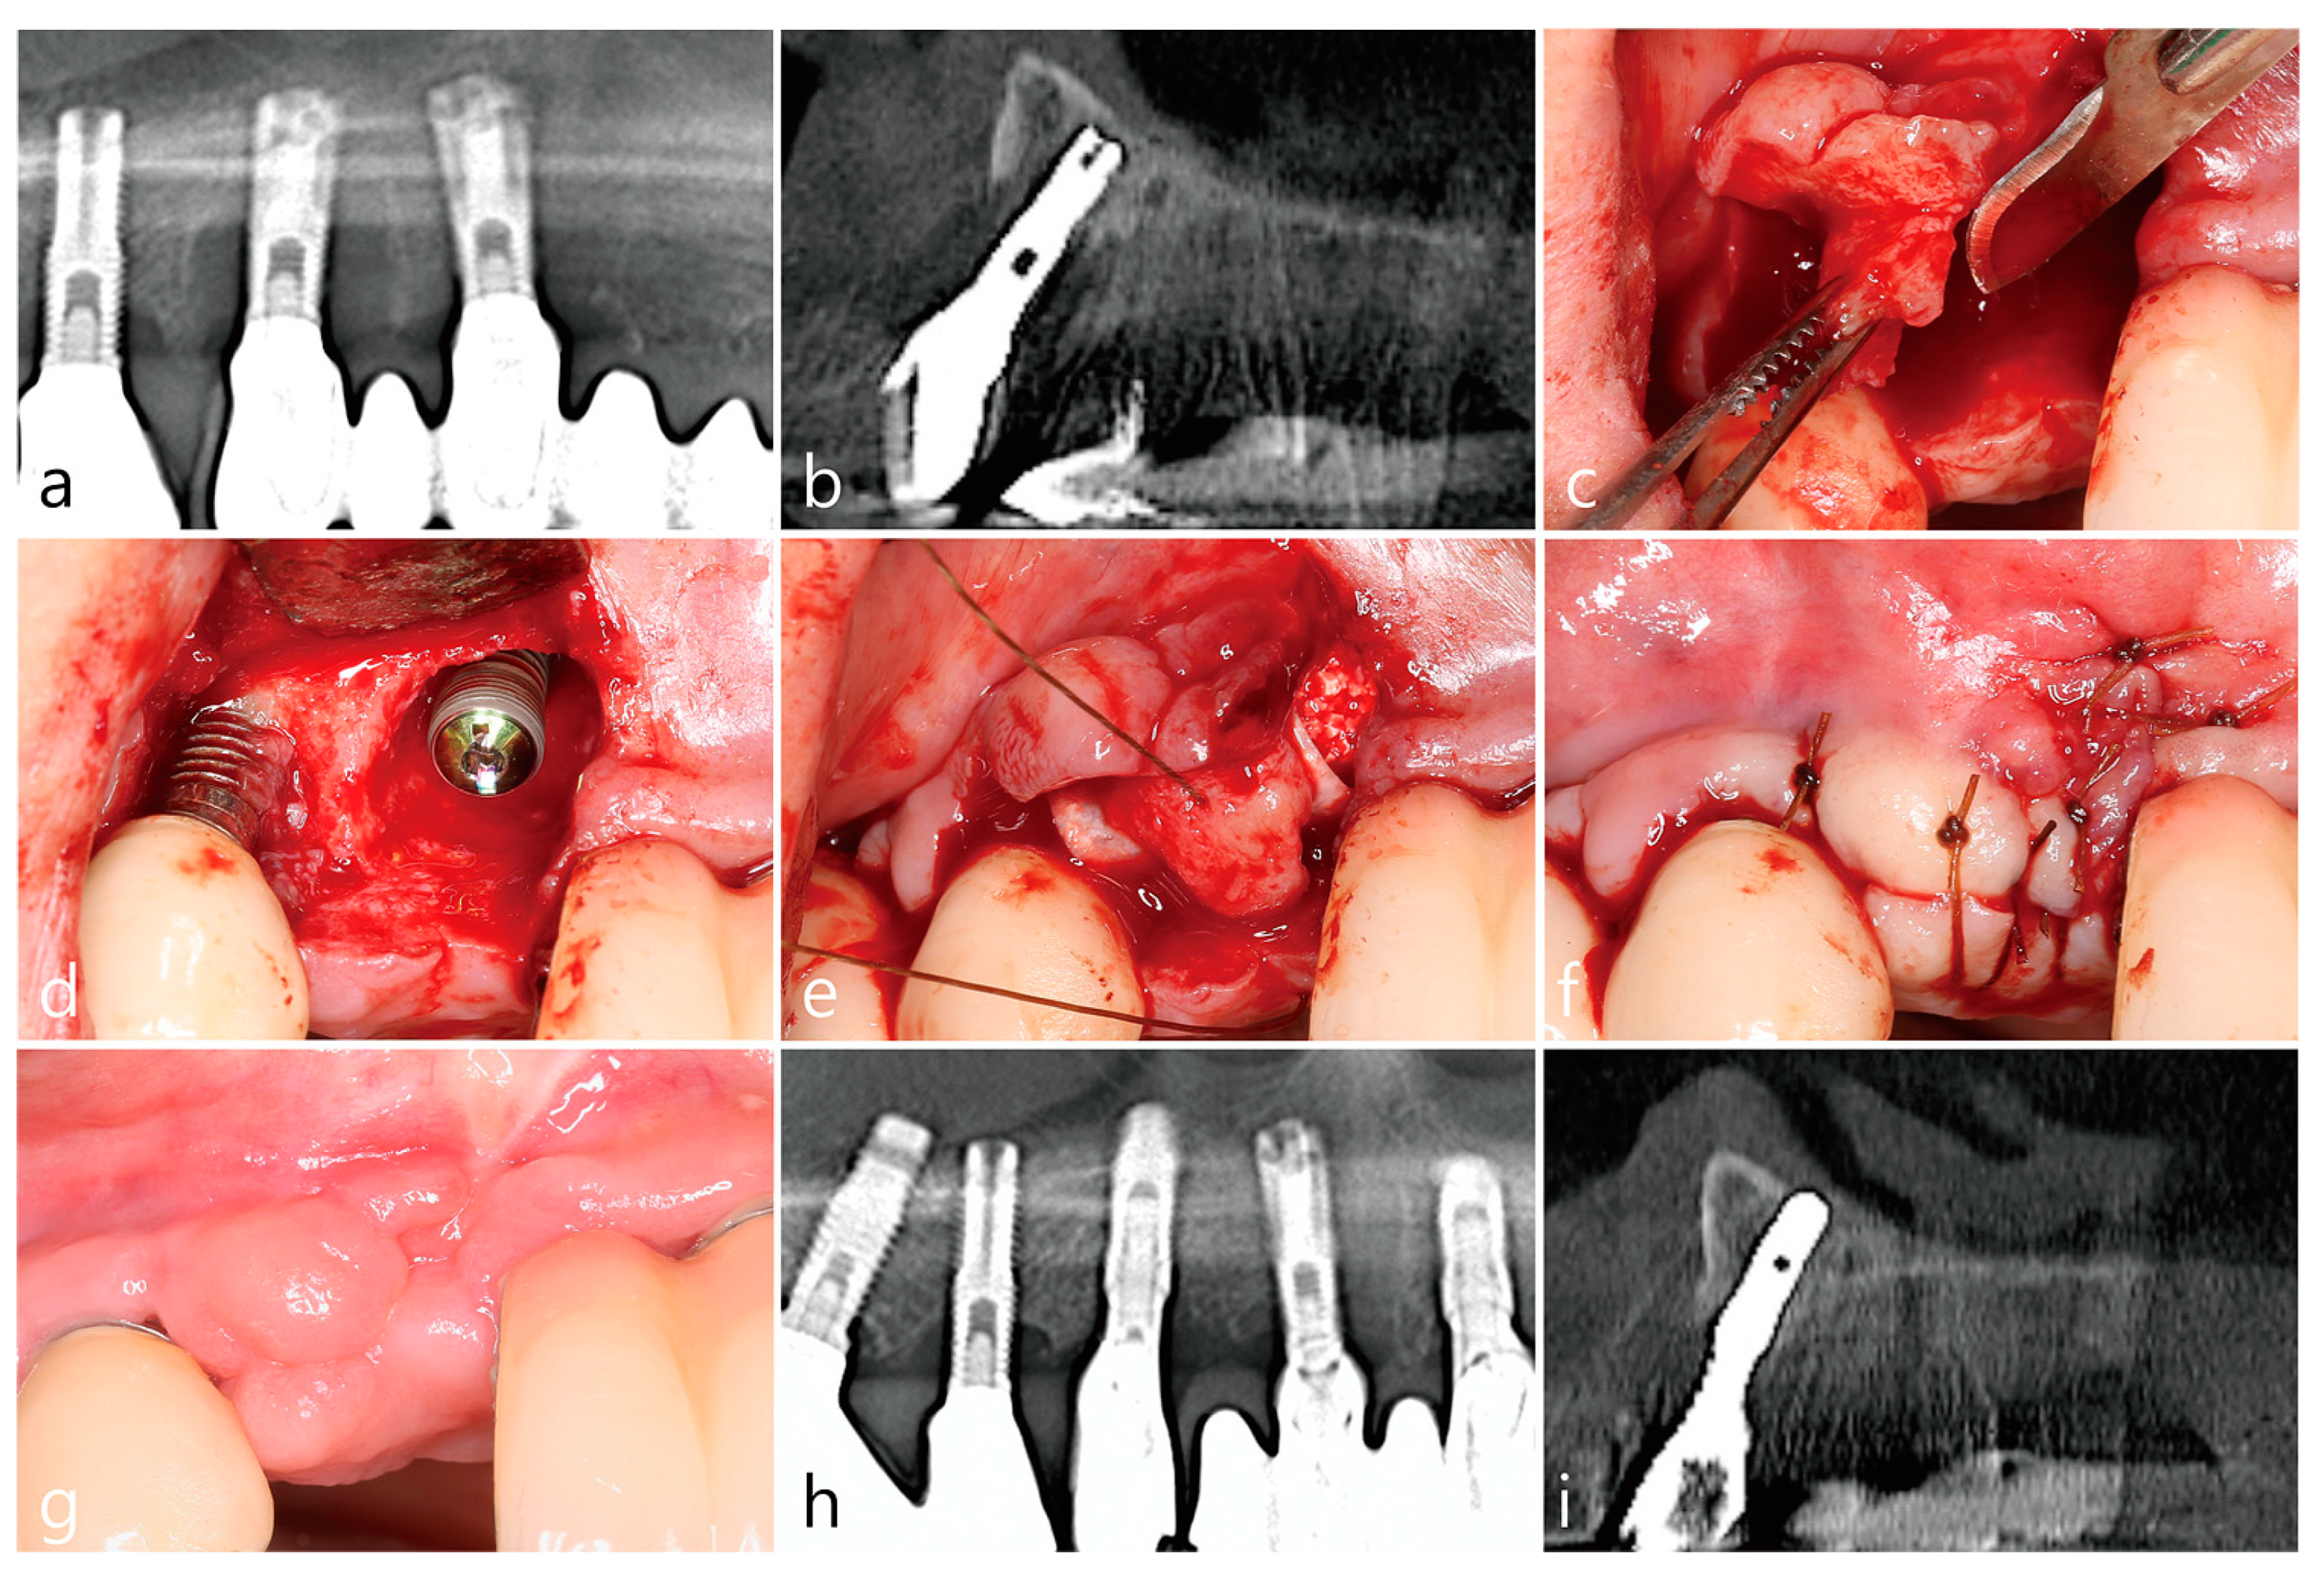

5. Case 3

- A tooth or implant with severe bone loss was removed using extraction forceps under local anesthesia with 2% lidocaine containing 1:100,000 epinephrine;

- A midcrestal incision and two buccal vertical incisions were made. Before raising the flap, special care was taken to ensure a clean dissection of the IGT from the underlying flap without any damage and the IGT is still well-attached to the flap. The IGT was then further separated from the bony housing by using a curette with various curvatures and a periosteal elevator.

- The IGT attached to the buccal flap was dissected to an appropriate thickness using a #15 blade so that the base of the IGT was still attached to the existing flap, and the flap was eventually extended. Periosteal releasing incisions were not performed at the flap base.

- The extraction socket was thoroughly debrided using a Molt curette and a titanium brush.

- A surgical guided stent was used so that the implant (Implantium, Dentium, Suwon, Korea) was placed 2.0 mm subcrestal to the level of the adjacent bone in the extraction socket.

- A synthetic osteoconductive bone graft substitute composed of hydroxyapatite (HA) and beta-Tricalcium phosphate (β-TCP) (Osteon III, Genoss, Suwon, Korea) and a resorbable collagen membrane (Genoss, Suwon, Korea) were placed to cover the implant and the peri-implant osseous defect.

- After covering the bone graft with the collagen membrane, the extended IGT was sutured with the palatal flap with 4-0 Catgut. Next, the buccal flap was closed using 4-0 nylon or black silk.

- Uncovering procedures were performed 4–6 months after initial surgery. Under local anesthesia, the buccal flap was reflected, the regenerated tissue above the implant cover screw was removed, and the healing abutment was connected to the implant. The buccal flap was closed using 4-0 Catgut or black silk. Antibiotics and anti-inflammatory drugs were prescribed for 5 days. The prosthesis was installed 2 months after uncovering.